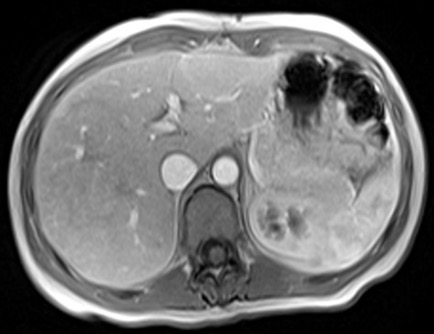

Aspetto RM

- Alterazione focale iso-ipointensa in T1, marcatamente iperintensa in T2, caratterizzata da un rapido e omogeneo enhancement in fase arteriosa senza wash-out, con ipointensità in fase epatospecifica.